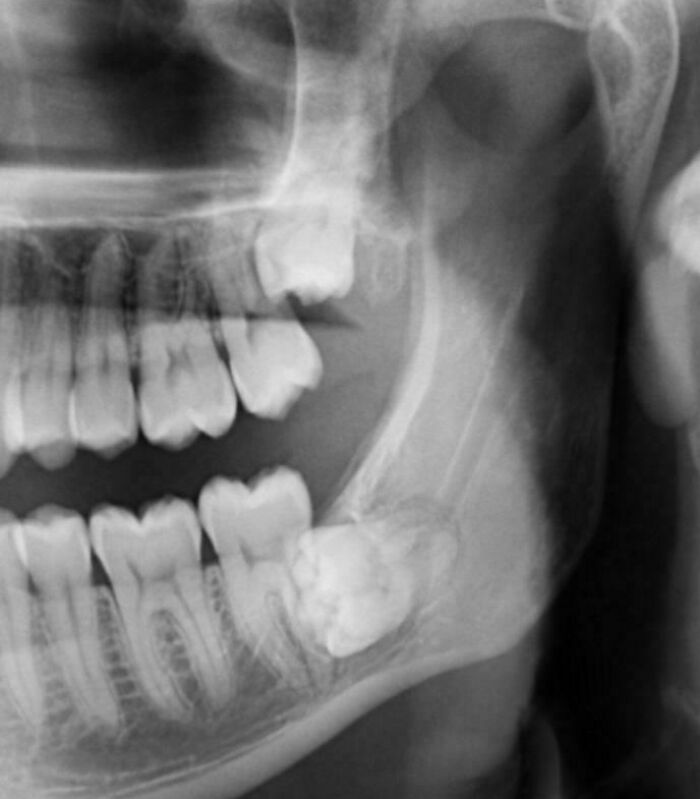

#16 My 6-Years-Old's Dental X-Ray